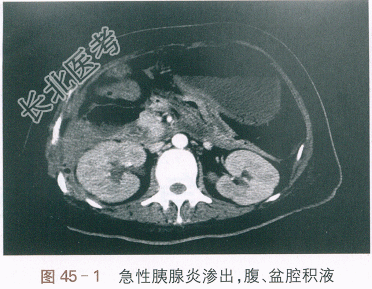

血常规:WBC16.51×10⁹/L,N91.2%,RBC3.27×10¹²/L,PLT257×10⁹/L。肝功能:TB/DB15.8/6.2(μmol/L),A/G30/29(g/L),ALT/AST232/294(IU/L)。肾功能:Scr132μmol/L,UA410μmol/L,BUN32.2mmol/L。CRP194.1mg/L;血钙1.75mmol/L;血甘油三酉旨10.9mmol/L。淀粉酶(AMY)390IU/L,脂肪酶245IU/L。血气分析:pH7.46,PaCO₂25mmHg,PaO₂71mmHg,HCO₃⁻18.6mmol/L,BE(B)-3.4mmol/L,SpO₂95%。腹部CT平扫提示:胰腺明显肿胀,边缘毛糙,周边及腹腔部分系膜、脂肪层结构模糊、密度增高,双侧肾前筋膜明显增厚,肝脏边缘光滑,胆管无扩张。考虑急性胰腺炎伴腹腔渗出,腹、盆腔积液(见图45-1)。胸部CT平扫提示:双侧少量胸腔积液,两肺下叶部分膨胀不全(见图45-2)。